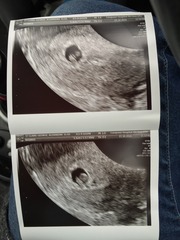

mrsunsure I had a scan and thought I was 6+5 but they said they only saw a sac and was more like 5 - here's the scan with just the sac, they said to come back in 10 days which were the longest 10 days of my life but I went back and they dated me as 6 weeks and saw a healthy heartbeat - here's the scan pic - fingers crossed for you, just remember that you only normally read the bad stuff on Google and all the forums but statistically you are more likely to have a healthy pregnancy than not - chin up xxx